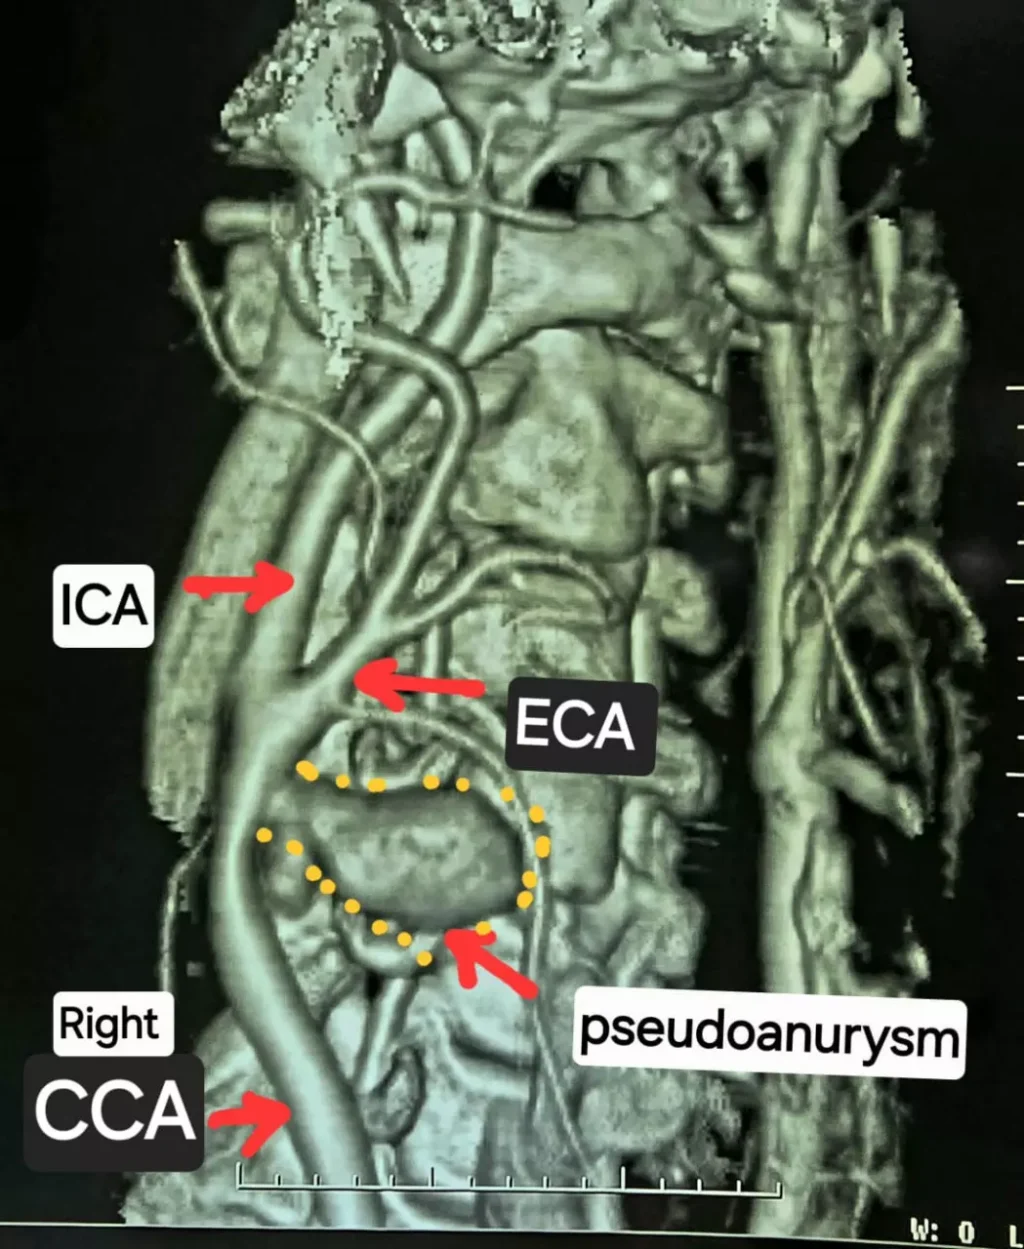

सीटी एंजियोग्राफी जांच में सामने आया कि मरीज की दायीं कैरोटिड आर्टरी फट चुकी है और उसके आसपास गुब्बारानुमा संरचना बन गई है, जिसे कैरोटिड आर्टरी स्यूडोएन्युरिज्म कहा जाता है। स्थिति की गंभीरता को देखते हुए मरीज को तुरंत हार्ट, चेस्ट एवं वैस्कुलर सर्जरी विभाग में डॉ. कृष्ण कांत साहू के पास रेफर किया गया।

कई घंटे तक चले इस जटिल ऑपरेशन में बोवाइन पेरिकार्डियम पैच की मदद से फटी हुई कैरोटिड आर्टरी की सफल मरम्मत की गई। सर्जरी पूरी तरह सफल रही और राहत की बात यह रही कि मरीज को किसी भी प्रकार का लकवा नहीं हुआ। वर्तमान में मरीज स्वस्थ है और सामान्य जीवन जी रहा है।